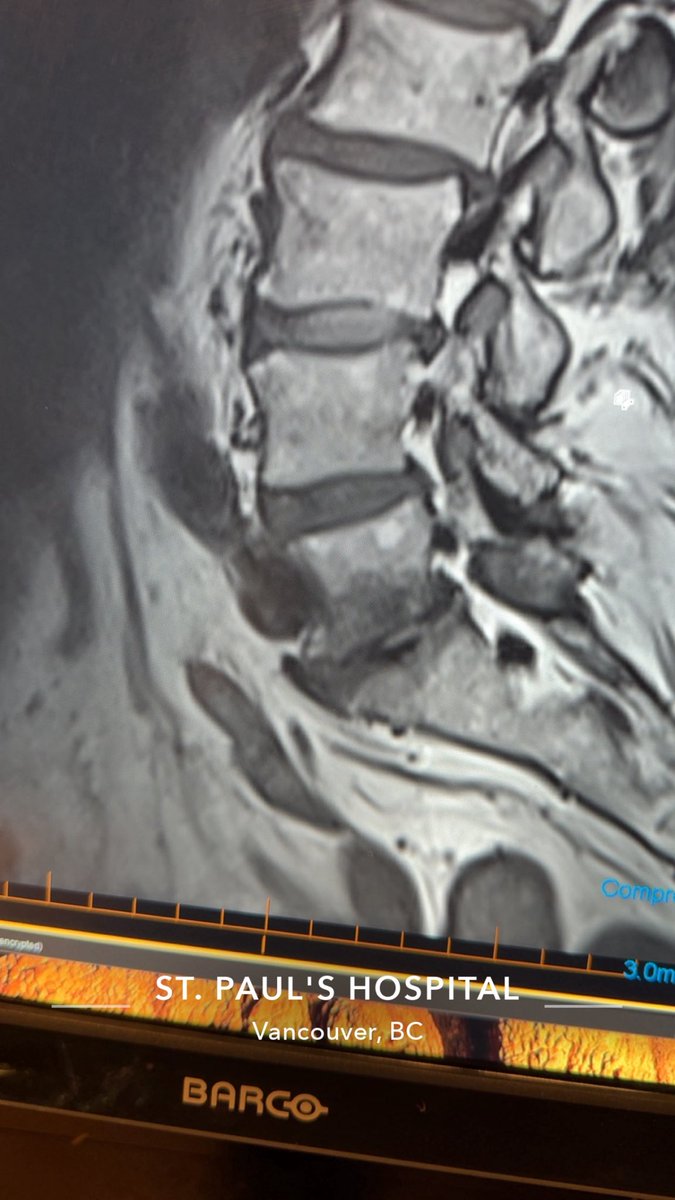

@Eyaaaad Ripcord suture

يلاحظ اجراء المريض لعملية انبوب للماء الازرق (لارتفاع ضغط العين)

وفيه حال كان الانبوب بدون صمام يتم وضع خيط داخل الانبوب وتركه في ملتحمة العين وذلك لازالته بعد اشهر

الخيط بعمل كـ flow resistance يبقي ضغط العين بالحد المعقول حتى لا يكون الضغط بعد العملية مباشرة صفر